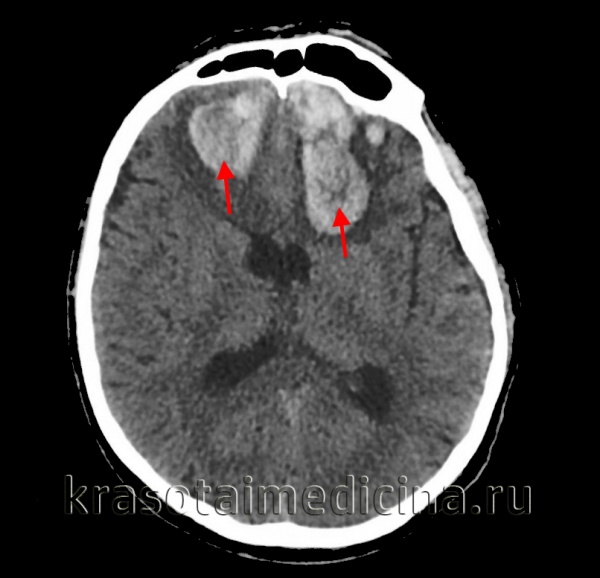

Иллюстрации и пояснения: гиподенсивный очаг на КТ головного мозга